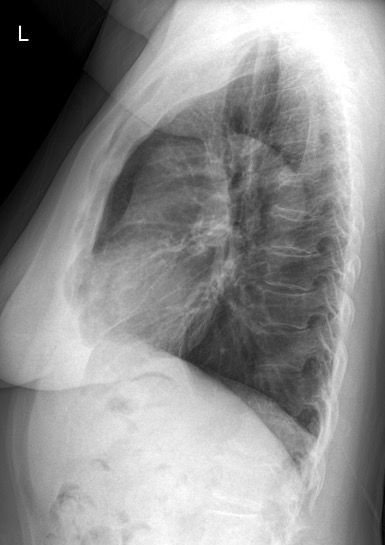

내과 엑스레이 소견 봐주세요..!!

내일 정밀 검사할 거긴 한데, 70대 여성으로 왼쪽 팔까지 통증 및 누워있을 때 통증이 더 심해지고 소화 불량, 토할 것 같은 느낌이 있습니다. 동네 병원 갔더니 큰 병원 가보라고 해서.. 이 사진 상으로 의심되는 게 있을까요?

올리신 사진의 엑스레이 소견에는 특별히 심각한 문제가 있어 보이거나 하지는 않습니다. 심장의 크기도 정상 범위로 보이며, 폐의 염증이나 기흉 등의 활동성 병변이 의심스럽거나 하지 않습니다. 엑스레이 소견만으로는 딱히 문제가 있고 어떠한 문제가 있는지 등 여부를 파악 및 판단하기 어렵겠습니다.